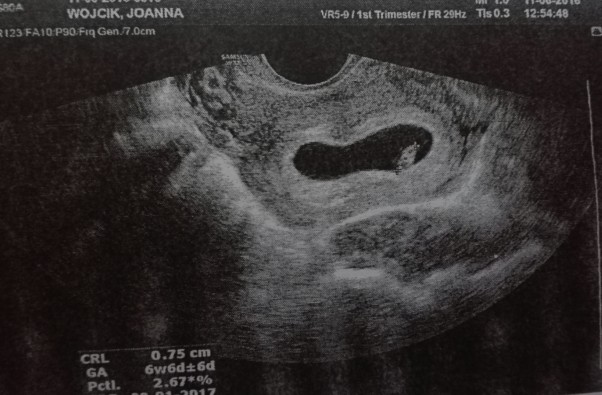

Ku wielkiemu zdumieniu wszystkich łącznie ze mną na ekranie monitora USG pojawia się mała fasolka. Lekarze wielokrotnie zapewniali mnie, że ciąża jest niemożliwa przy tylu schorzeniach. Niepewność i łzy, ale i wielkie szczęście..... Jeszcze za wcześnie by malować pokój na różowo, ale to na pewno będzie zdrowa śliczna dziewczynka :).